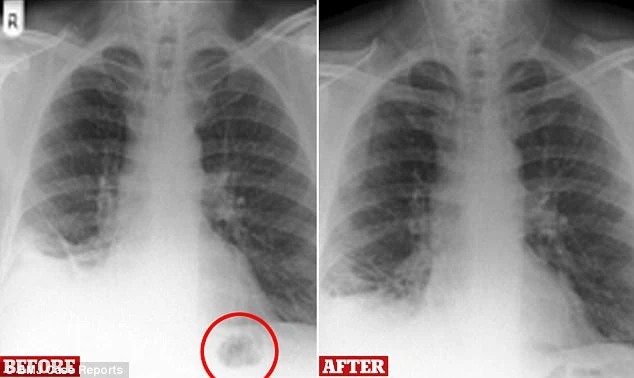

Người đàn ông giấu tên, 47 tuổi, hiện đang làm công việc tạp vụ cho biết, trong một năm gần đây ông thường xuyên bị ho, và cảm thấy không được khỏe. Phim chụp X-quang cho thấy ông này có một khối u nhỏ trong phổi, cùng với việc ông đã hút thuốc khá nhiều trong suốt 30 năm, các bác sĩ chẩn đoán ông ta có thể bị ung thư.

Phim chụp X-quang cho thấy có một khối u gần cạnh phổi bệnh nhân. Ảnh: BMJ